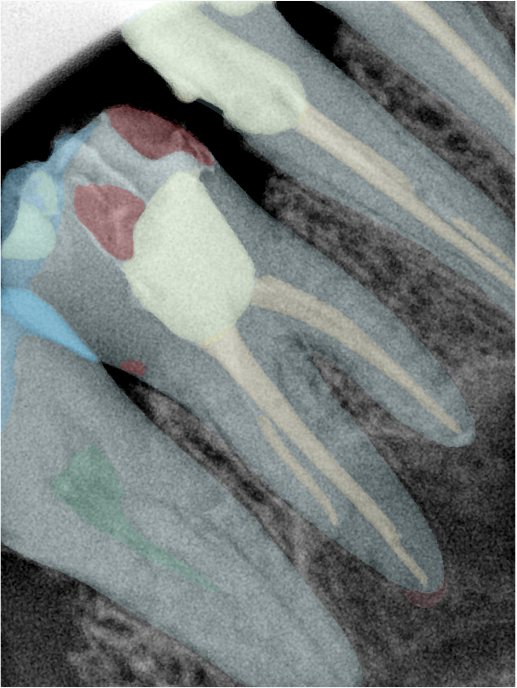

第二版算法问题测试

| 第一版 | 第二版 | 是否解决 | |

|---|---|---|---|

![]() | ![]() ![]() 边角识别有问题 龋齿识别不全 牙髓识别不全 | ![]() | 解决 |

![]() | ![]() 边角识别有问题 识别信息有误 自查(牙冠识别不全) | ![]() | 解决 |

![]() | ![]() ![]() 边角识别有误 大范围填充识别遗漏 | ![]() | 解决 |

![]() | ![]() 识别信息不全 | ![]() | 解决 |

![]() | ![]() ![]() 边角问题 牙胶识别不全 牙冠识别不全 | ![]() | 解决 |

![]() 换图片 | ![]() | ![]() 牙冠部分稍微白了一些就识别成小范围修补,部分判断异常 | 部分解决,修复类略敏感,牙冠部分稍微白了一些就识别成小范围修补,部分判断异常。 |

![]() | ![]() ![]() 牙冠识别不全 牙髓不全 根尖炎龋齿识别有误 | ![]() | 解决 |

![]() | ![]() | ![]() | 解决 |

![]() 换图片 | ![]() | ![]() | 解决 |

![]() | ![]() 牙冠识别有误 | ![]() | 解决 |

![]() 换图片 | ![]() ![]() 边角识别有误 | ![]() 修复类敏感 | 部分解决,图像过白,导致修复类判断异常。 |

![]() 换图片 | ![]() 牙冠识别不全 | ![]() 修复类敏感 | 部分解决,图像过白,导致修复类判断异常 |

结论:修复类出现了不鲁棒的情况,后续需要加入轮廓的扩充数据进行增强。